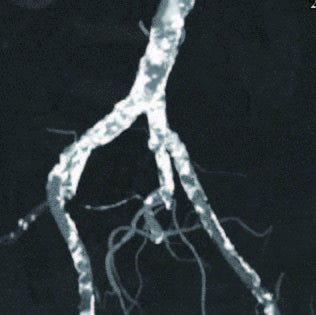

術前造影画像

狭窄はないが高度石灰化があるため両側総大腿動脈からの穿刺を回避して左橈骨動脈アプローチを選択した。5 Frシースを留置後、型通りに腹部大動脈までシステムを下降させ造影を施行し、左外腸骨動脈起始部に高度石灰化病変を確認した(図1a)。